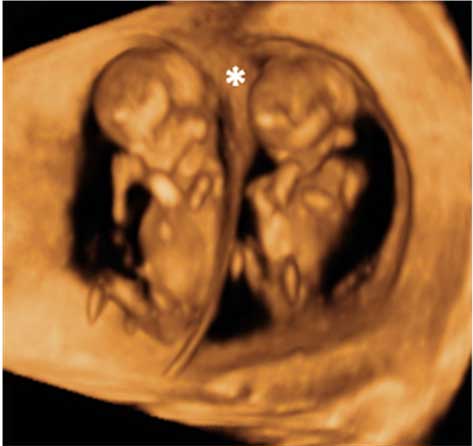

Ecografía 3D de semana 11: Feto de perfil

Se distingue el sexo del feto

Las ecografías permiten distinguir el sexo del feto. En este ultrasonido en 3D, el bebé de 11 semanas de gestación se cree que es una niña, aunque no se puede asegurar todavía. Los genitales externos se empiezan a formar en la semana 8 de embarazo y terminan hacia la semana 12.

Perfil en ecografía 3D de un feto de 11 semanas

El tubérculo genital (flecha) apunta hacia abajo, lo que hace muy probable que se trate de una mujer.